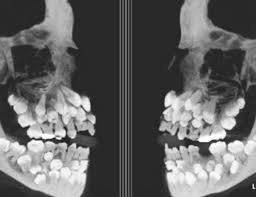

ÀϺ»¿¡¼ °³¹ß ÁßÀ̶ó´Â ÀÓÇöõÆ® »óÀ§È£È¯ ¿µ±¸Ä¡¾Æ.jpg

1. Àΰ£µµ »ç½ÇÀº »ó¾îó·³ ¿µ±¸Ä¡°¡ ºüÁ®µµ °è¼Ó »õ À̰¡ ÀÚ¶ö ¼ö Àִ ȯ°æÀÓ

2. ±Ùµ¥ USAG-1 À̶ó´Â ´Ü¹éÁú»õ³¢°¡ »õ À̰¡ ÀÚ¶óÁö ¸øÇÏ°Ô ¸·°íÀÖÀ½

3. ±×·¡¼ ±× USAG-1 À̶ó´Â ´Ü¹éÁú»õ³¢¸¦ Á¸³ª ÆÐ¼ »õ ¿µ±¸Ä¡°¡ ³¯ ¼ö ÀÖµµ·Ï ¸¸µå´Â°ÅÀÓ £¨Áã, ÆÐ·µ ½ÇÇè ¼º°ø£©